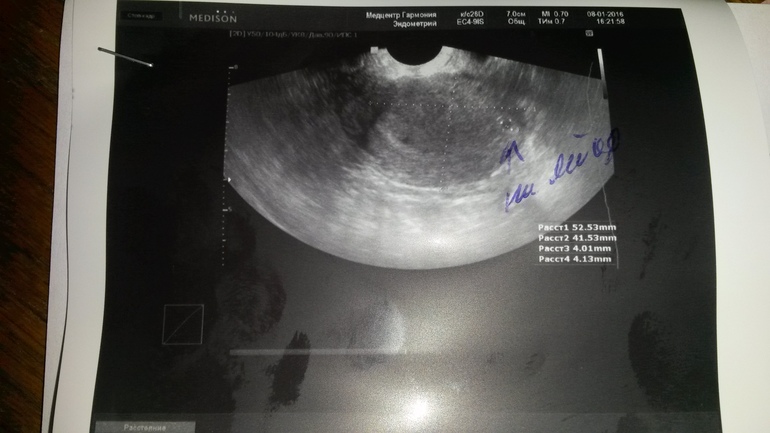

О была 15.12, тесты заполосптились в день Х (28.12), сровнялись полосочки 3.01. Но тянет немного правый бок, да еще и отравилась первого числа. Пошла сегодня на узи... выходит на 12 день задержки пл.яйцо 4мм... говорит что соответствует сроку 2-3 недели, а должно быть больше. Неужили все действительно плохо?

у меня тоже точь в точь, как у вас, 15-го овуляция, но первые полоски увидела уже 25-го. позавчера была на узи, поставили 4 недели и ПЯ 7 мм. Я думаю, ничего страшного, не так уж и мало, может у вас просто имплантация была позже. Важно в динамике понаблюдать. Ну и за собой понаблюдайте, за ощущениями, у меня вот например день ото дня токсикоз все сильнее и сильнее, значит с бусинкой все ок и она растет и развивается)

У меня О и день Х такие же, 4го полоски сровнялись, 4го пошла на узи- поставили 4 недели, плодное яйцо 6.4 мм. Может у вас и у меня это всё в пределах нормы?

вот результаты